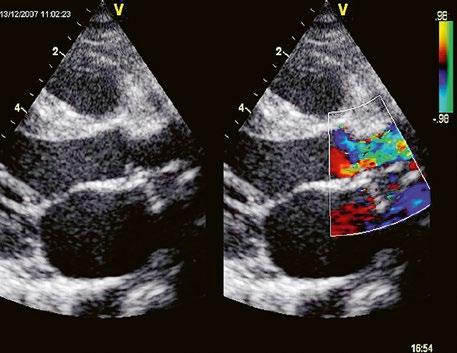

Obr. 45.36 Valvární pulmonální stenóza, doming cípů, jemné cípy, srůst komisur (TEE, longitudinální projekce) AP – kmen plicnice, PK – pravá komora, PS – pravá síň

Echokardiografie a jícnová echokardiografie (TEE) je hlavní diagnostickou metodou se zhodnocením morfologie chlopně (Obr. 45.36, Obr. 45.37, Obr. 45.38, Obr. 45.39, Video 45.38), pravé komory (Obr. 45.44) i gradientu (Obr. 45.45). Samotný gradient může být při nevhodném úhlu podhodnocen a je třeba ho korelovat s gradientem na trikuspidální regurgitaci. V dospělosti může mít i významná PS nižší gradient při dysfunkční